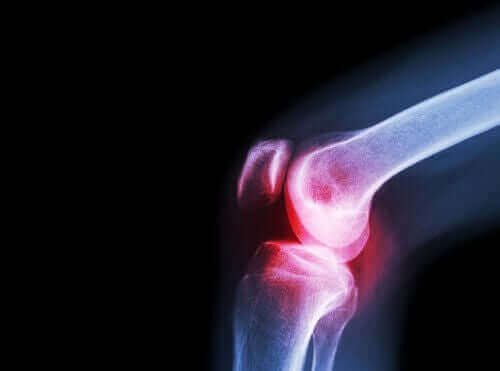

Revmatoid artritt er en kronisk inflammatorisk autoimmun sykdom. Denne sykdommen påvirker flere ledd og har forskjellige generelle og ikke-spesifikke symptomer.

I form av symptomer manifesterer revmatoid artritt seg vanligvis med smerter og stivhet, samt vanskeligheter med å bevege forskjellige små og store ledd.

Leger anbefaler også aceklofenak mot denne tilstanden. Slitasjegikt er en annen revmatisk sykdom som skader leddbrusk.

Leddene inneholder en væske som er kjent som synovialvæske som synovialmembranen produserer. Endene av benene som kommer sammen for å danne et ledd er dekket med leddbrusk.

Når denne brusken opplever skader, forårsaker det smerter, stivhet og funksjonshemning. Det er derfor viktig å skille denne sykdommen fra leddgikt. Sistnevnte utvikler seg på grunn av leddbetennelse, ikke bruskslitasje.